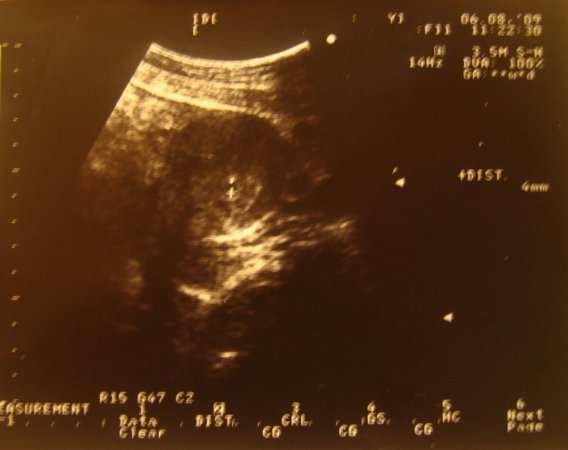

<div id="msgcns!CDD546D95B4BBC70!920" class="bvMsg"> <a href="http://wz9jiq.bay.livefilestore.com/y1pH_Dg-mKxxOnOHRhSph_R9lQx3i_k0J_J0VdF5fHvMfPLZIfAz-5Yd_pAwlKQCmzCCVX8LAOF42of7BNJXGYID-wQTwSwyQUY/%E5%B0%8F%E7%8E%89%E7%B1%B3.jpg" title=""><img alt="" src="http://pic.pimg.tw/itswolf/eb6627d35eb088400364edf8588a5c93.jpg?v=1292312691" width="568" height="450" /></a><br /><font style="font-family:標楷體" size="3"><br />小玉米預計將於 <strike>2009</strike> 2010/02/04上市,敬請期待 XD<br /><br />話說戴小姐在五月中做例行姓婦科檢查,發現有巧克力囊腫<br />害怕開刀的他嚇得要死<br /><br />醫生建議巧克力囊腫不處理的話,可能會導致卵巢萎縮,進而影響生育<br />再者,有巧克力囊腫受孕會比較困難<br />又再者,懷孕因為十個月沒有月經,可能巧克力囊腫會自己改善<br /><br />基於以上理由,戴小姐說那咱們別避孕吧<br />然後兩個禮拜後,醫生就跟我們說<font size="7"><span style="color:rgb(255, 0, 0)">恭喜老爺賀喜夫人</span></font>了<br />我只能說 我</font><font style="font-family:標楷體" size="3">真是</font><font style="font-family:標楷體" size="3">他X的身體好啊 Orz</font><br /> <br /> <br /> <br /></div>